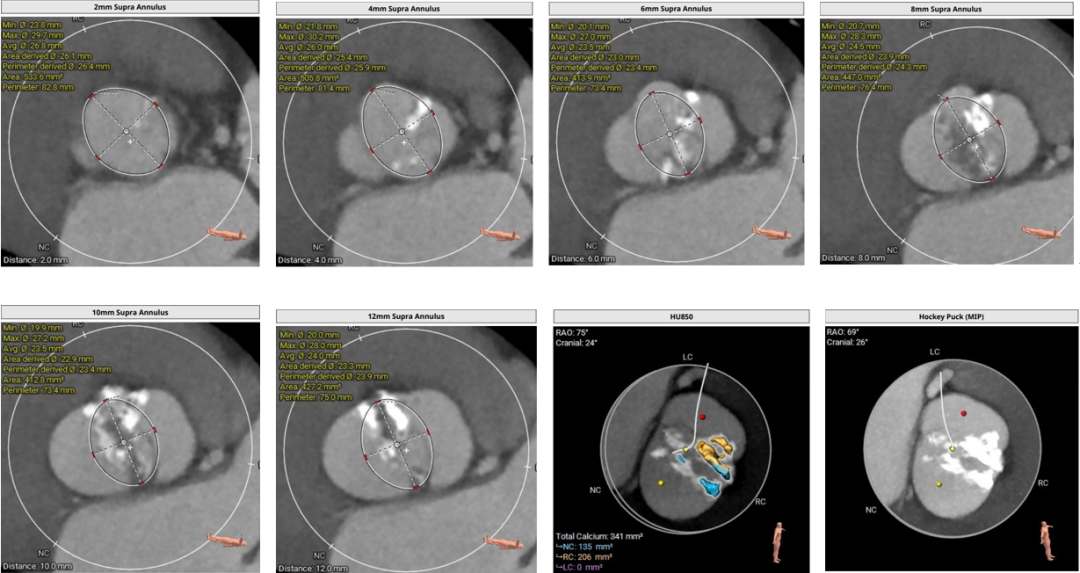

术前评估:

1.主动脉瓣瓣环周长80.9mm,平均周长径25.8mm;

2.Type0型二叶式主动脉瓣,中度钙化,瓣叶增厚,左室流出道呈收口状;

3.左右冠共窦,冠脉开口高度可,左、右冠瓣叶长度<冠脉开口到瓣叶附着缘距离;

4.瓦式窦、窦管交界、升主动脉内径尚可;

5.瓣环水平夹角66°,横位心,主动脉弓宽度、角度可;

6.双侧外周入路行走适宜,未见明显迂曲。

主动脉根部评估:

图片